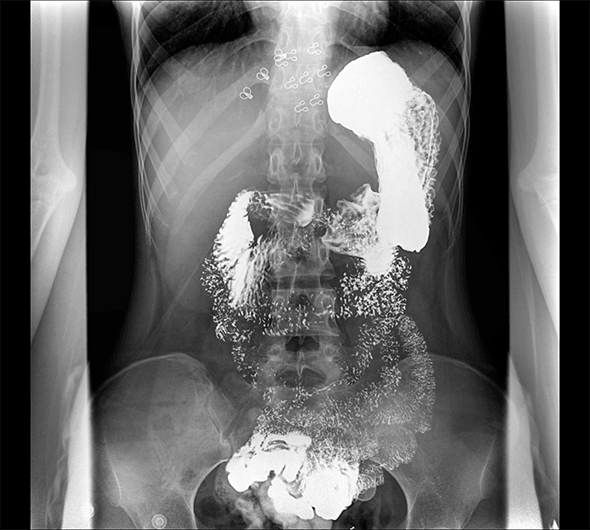

临床图像

创新动态断层多功能胃肠 DR 系列